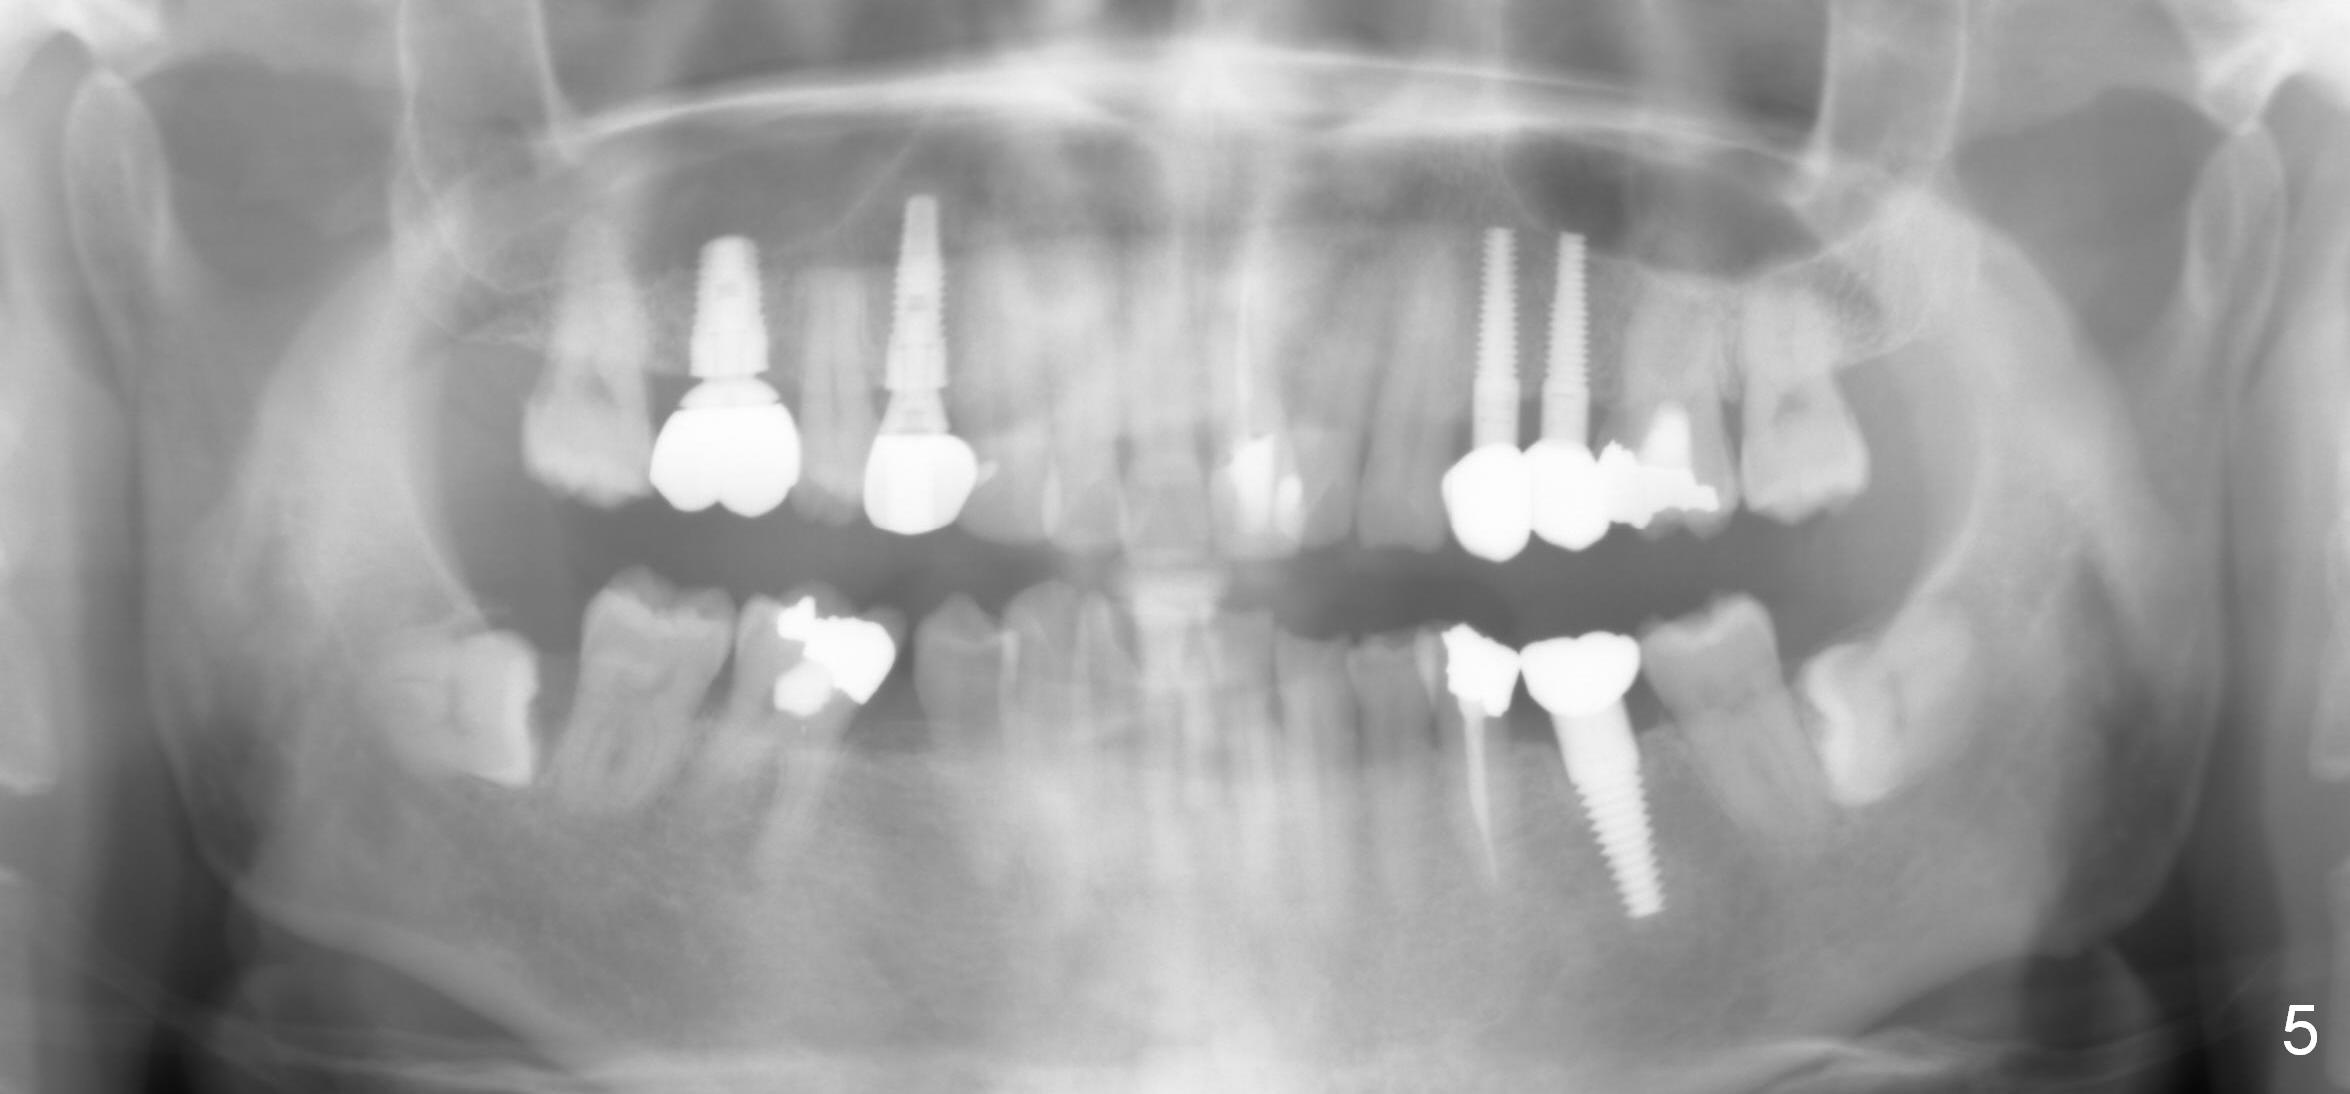

There is no relapse of intrusion for 2 years (Fig.5; also 2 years (for #12,13,30) and 7 months (3,5) post cementation).